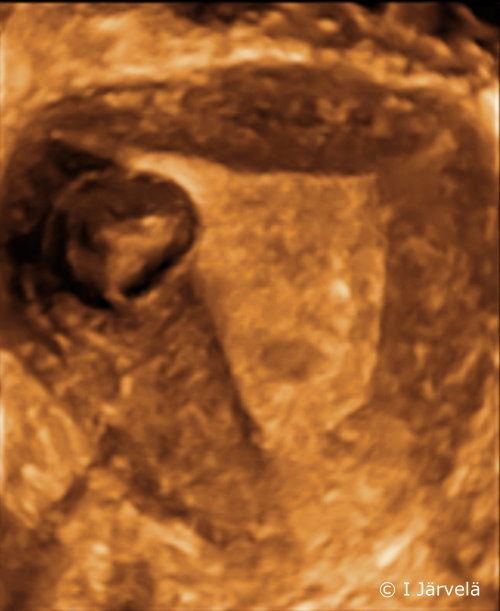

Submucosal Myoma (Ultrasound Scan)

Submucosal myoma (ultrasound scan).

Picture: Ilkka Järvelä; text: Dimitrios Scordas